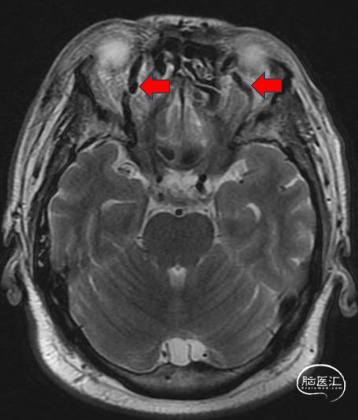

右侧颈内动脉海绵窦瘘(Brrow A型)。

前交通开放,左侧大脑前动脉通过前交通动脉向右侧前循环供血。

右侧后交通开放,后循环通过后交通动脉向右侧前循环供血。